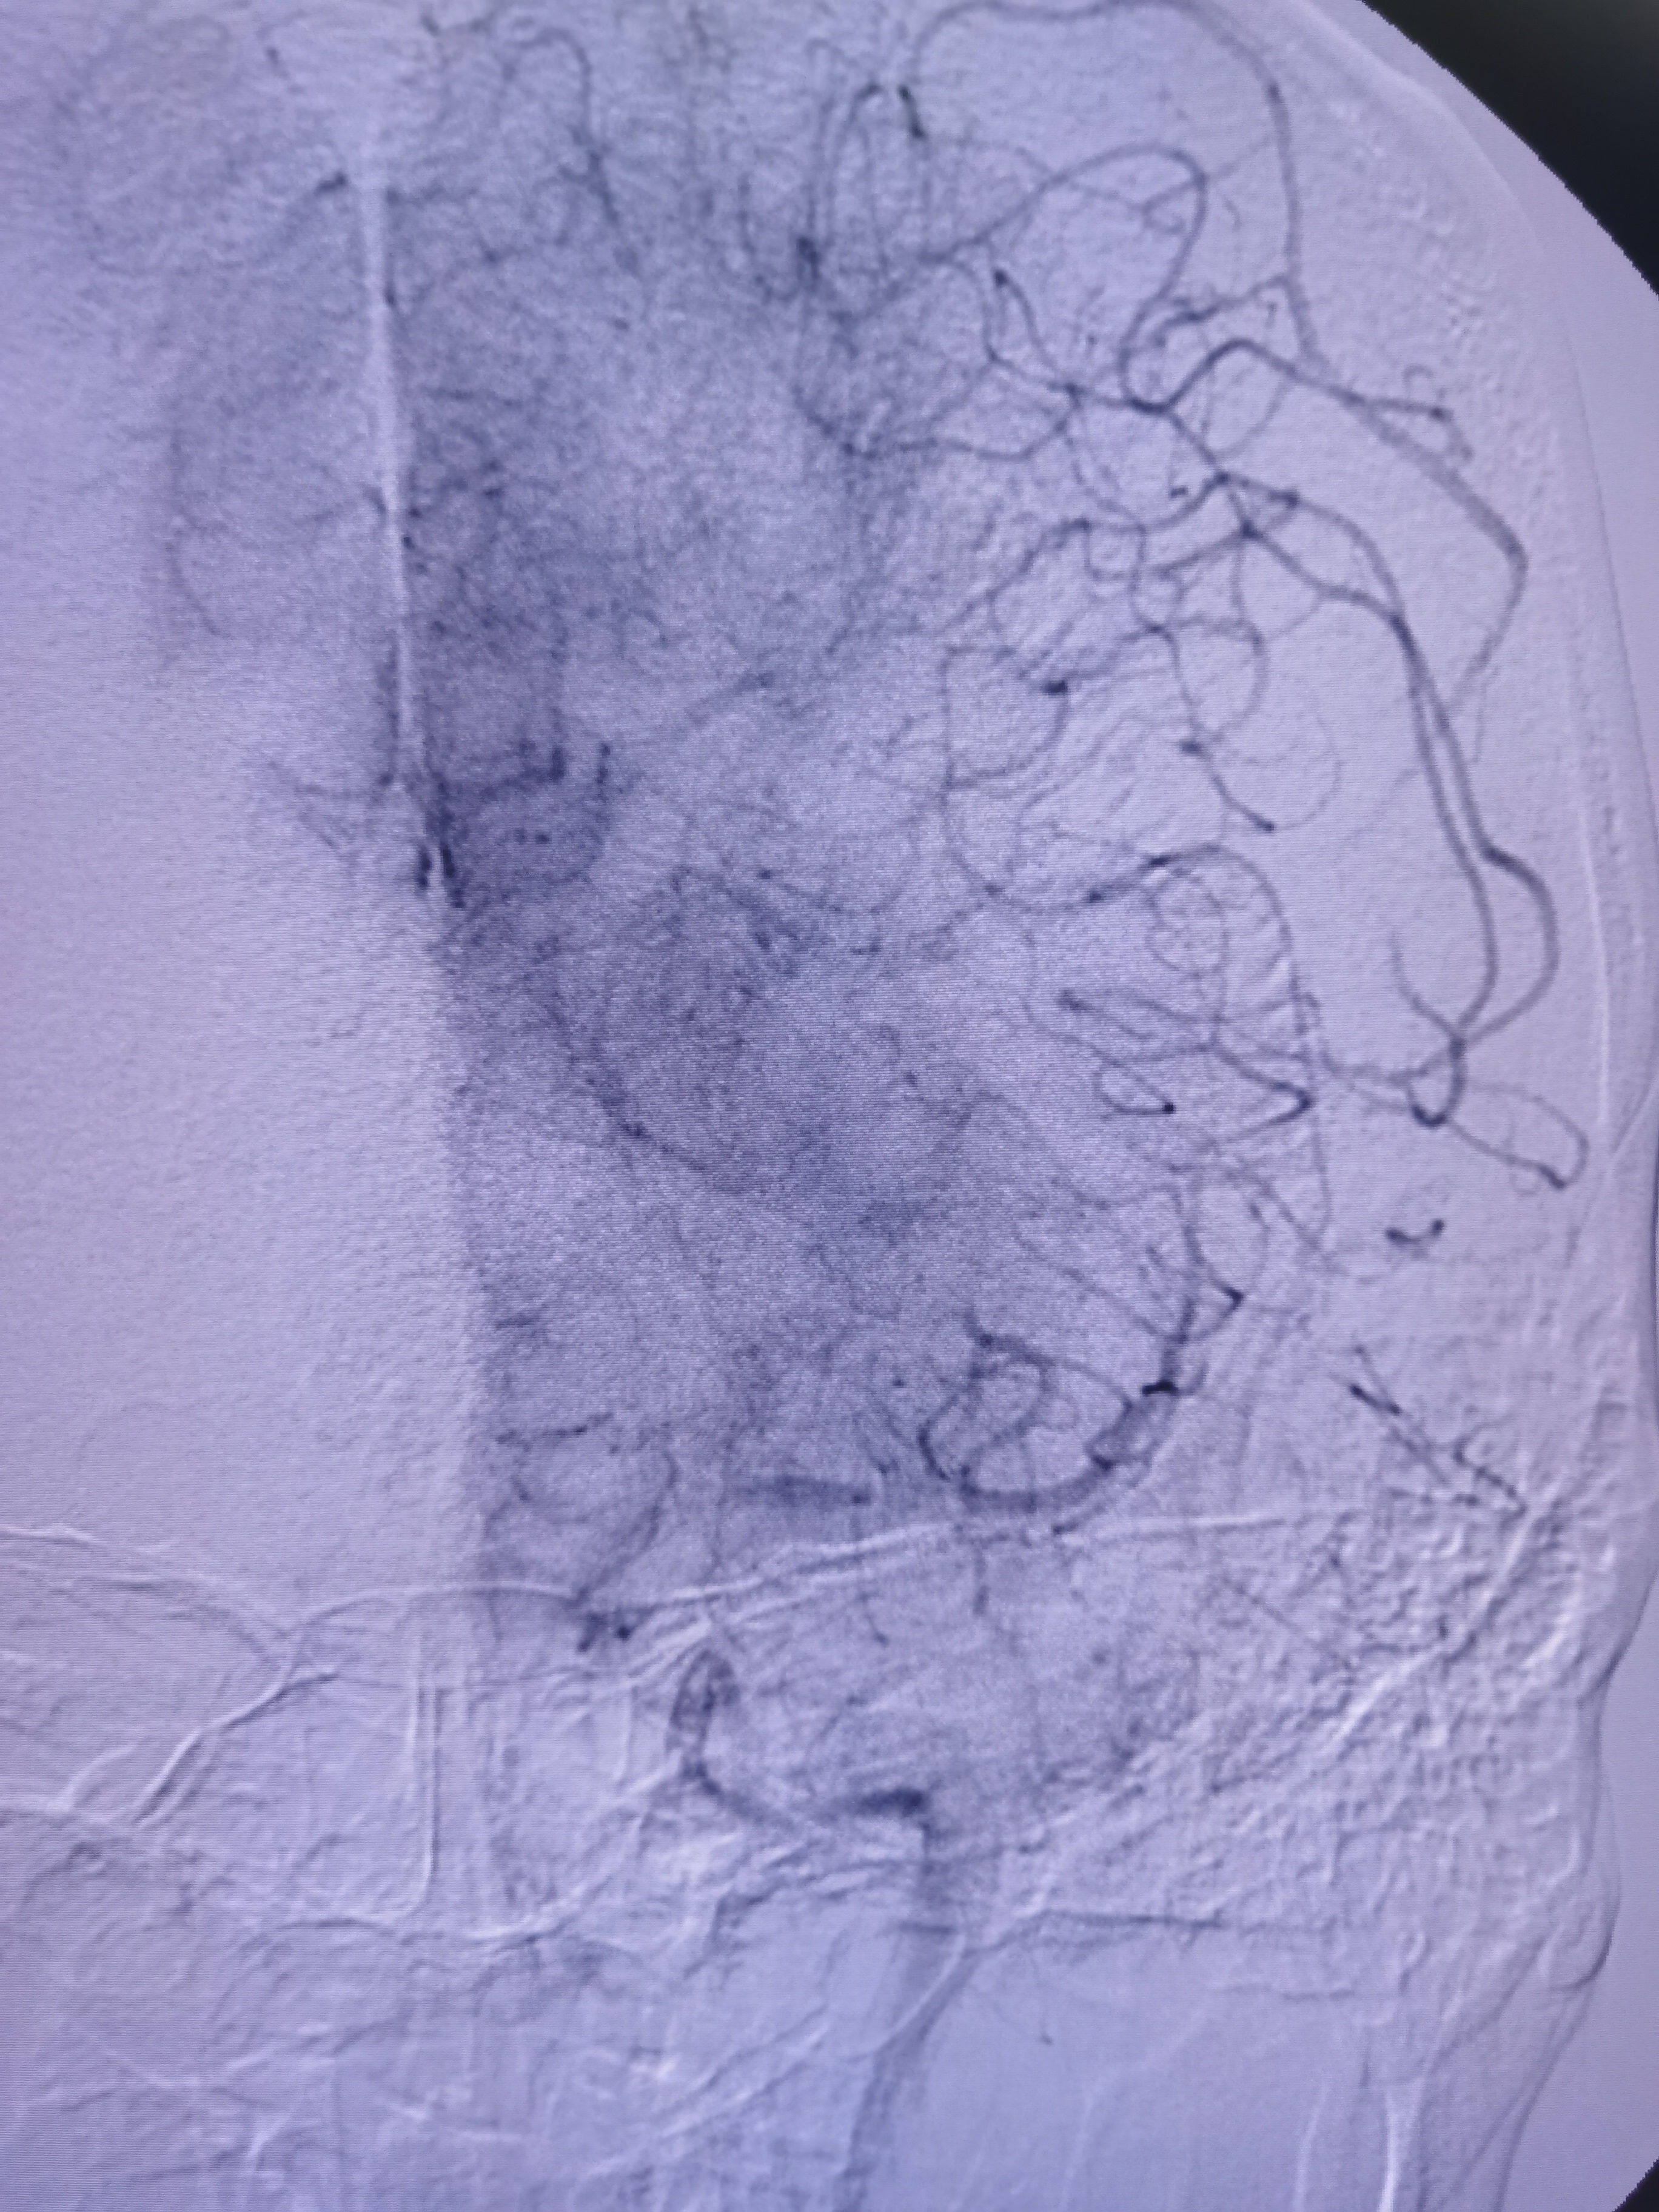

左侧大脑中动脉闭塞,胚胎型大脑后动脉。

动脉晚期可见软膜支代偿远端血供。